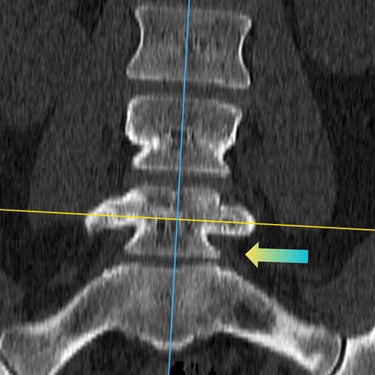

🧠 Listesis L4–L5 con Estenosis Severa: Estabilización con Fijación Transpedicular (FTP) y Fusión Intersomática Transforaminal (TLIF)

La listesis L4–L5 con estenosis severa provoca dolor lumbar e inestabilidad con compresión nerviosa. La fijación transpedicular (FTP) y la fusión intersomática transforaminal (TLIF) permiten descomprimir el canal espinal, estabilizar la columna y mejorar la función de forma segura y progresiva.